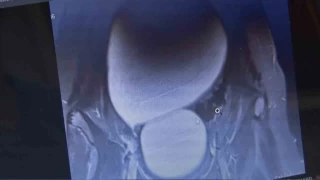

Sivas'ta yaşayan 12 yaşındaki N.B. şiddetli karın ağrıları ve düzensiz adet kanamaları şikayetiyle hastaneye başvurdu. Yapılan detaylı tetkikler sonucunda genç kızın karın bölgesinde yaklaşık 25 santimetre çapında adeta kavun büyüklüğünde bir kist olduğu tespit edildi. Medicana Sivas Hastanesi'nde Çocuk Cerrahisi Uzmanı Op. Dr. Mahmut Aluç tarafından gerçekleştirilen başarılı bir operasyonla, genç kızın sol yumurtalığında bulunan ve karaciğere kadar uzanan devasa kist içerisindeki 1.6 litre su boşaltılıp, başarıyla çıkarıldı. Sağlığına kavuşan genç kız taburcu edildi.

Çocuk Cerrahisi Uzmanı Op. Dr. Mahmut Aluç, kisttin içerisinden yaklaşık 1.6 litre sıvı boşaltıldığını söyleyerek, ' Karın ağrısı, düzensiz adet şikayetiyle bize geldi. Dışarıda yapan tetkiklerde ve bizde yapılan tetkiklerinde karın içerisinde yaklaşık yirmi beş santimetrelik çapında bir kitli kitle tespit ettik. Burada da tetkiklerimize tekrar baktığımızda sol över kökenli bir kisttik yapı olduğunun farkına vardık. Gerekli incelemeleri yaptıktan sonra ve ailenin onayını aldıktan sonra hastayı operasyona aldık. Karaciğere kadar uzanan bir kisttik yapımız vardı. Onun içerisinde yaklaşık 1.6 litre sıvı boşalttık. Over dokusunu, yumurtalık dokusunu koruyarak kisti tamamen eksize ettik. Hastamızı şifayla taburcu ettik. Patoloji sonucumuz da iyi huylu olarak geldi' dedi.'İlk adetin başladığı ergenlik çağında olan overkistlerin daha yakın takip edilmesi lazım'